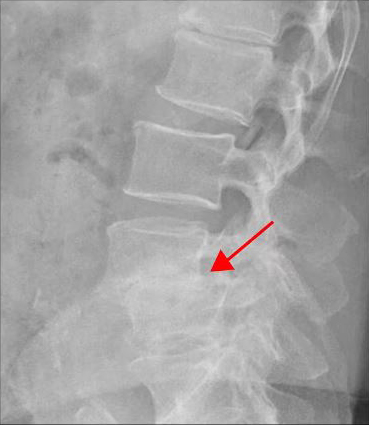

<4-5번 추간공협착증>

이 환자분의 허리 MRI를 보면 4번, 5번 오른쪽에 심한 추간공협착증과 2단계의 척추전방전위증이 있는데, 특히 척추전방전위증 때문에 추간공이 많이 좁아져 있는 상태입니다. 또 왼쪽의 다른 마디에 디스크 파열이 있으나 환자분이 왼쪽으로는 증상이 전혀 없는 것으로 보아 이 디스크 파열은 통증을 일으키지 않는 무증상의 디스크 파열입니다.

이렇듯 4번, 5번 마디의 심한 추간공협착증과 척추전방전위증으로 인해 이 환자분은 다리에 마비가 왔고, 발목에 힘이 빠져 거의 걷지 못하는 상태였습니다. 새벽에 잠에서 깨 화장실을 갈 때는 네 발로 기어갈 정도로 증상이 심했습니다. 신경주사도 많이 맞아봤지만 통증이 전혀 줄지 않아서 결국 수술을 결심하셨는데요. 대학병원을 비롯해 정형외과 및 신경외과 등 아홉 군데 병원에서 진료를 받았지만, 어려운 수술이라고 말하면서 척추유합술, 감압술 등 병원마다 제시하는 수술방법이 다 달라 큰 혼란을 겪으셨습니다. 게다가 수술 후 후유증이나 잔존 증상에 대한 물음에 ‘있을 수도 있고 없을 수도 있다’라는 의사의 말에 수술을 고민하던 중 마지막이라는 생각으로 저희 모커리에 내원하셨습니다.